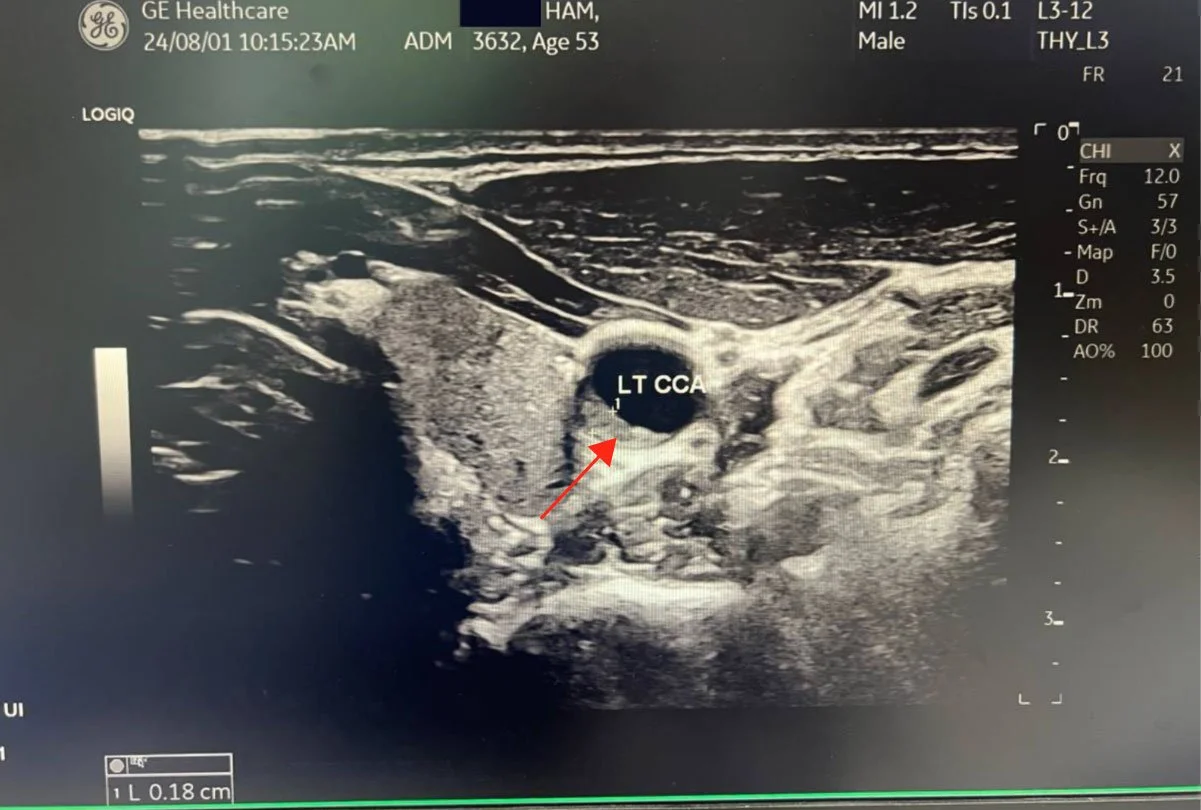

As you may know, I had bilateral plaque in the carotid arteries, now all gone. It seems almost miraculous, so I am studying the studies to understand the mechanism of how and what happened for such a remarkable result. I have reviewed the major carotid artery studies on exercise.

After thinking how I reversed my carotid plaque from May 9, 2025 (Started WFPB Esselstyn diet) to August 19, 2025, when my carotid ultrasound showed that all my plaque was gone and CIMT reduced 53%, I have been trying to understand the mechanism and biochemical pathways this occurred. I have been so focused on diet, that I wondered how much my 3000 km of cycling played a role. I did three Gran Fondo (120+ km) rides last year. Then after my September fondo, I basically stopped riding. My coronary plaque did not really reverse after that, although blood flow improved remarkably. So that has made me curious.

The carotid ultrasound at three months showed something I had hoped for but had not been certain enough to expect: both carotid arteries were completely clear. Not reduced. Clear. The plaques had resolved bilaterally in just three months. And the CIMT, the intima-media thickness that had read like an 85-year-old when I started, crossed into high-normal for age 55. By month ten, it was mid-normal. A 53% bilateral reduction in carotid arterial wall thickness, confirmed on imaging another three times afterwards, always improving.

I wondered about this for months. Both carotid plaques had vanished on imaging in three months. The coronary plaque had not moved structurally, though the FFR had improved from 0.75 to 0.80, from a stentable reading to a low-normal one. Something was changing in the coronary territory. But not the same thing, and not at the same speed.